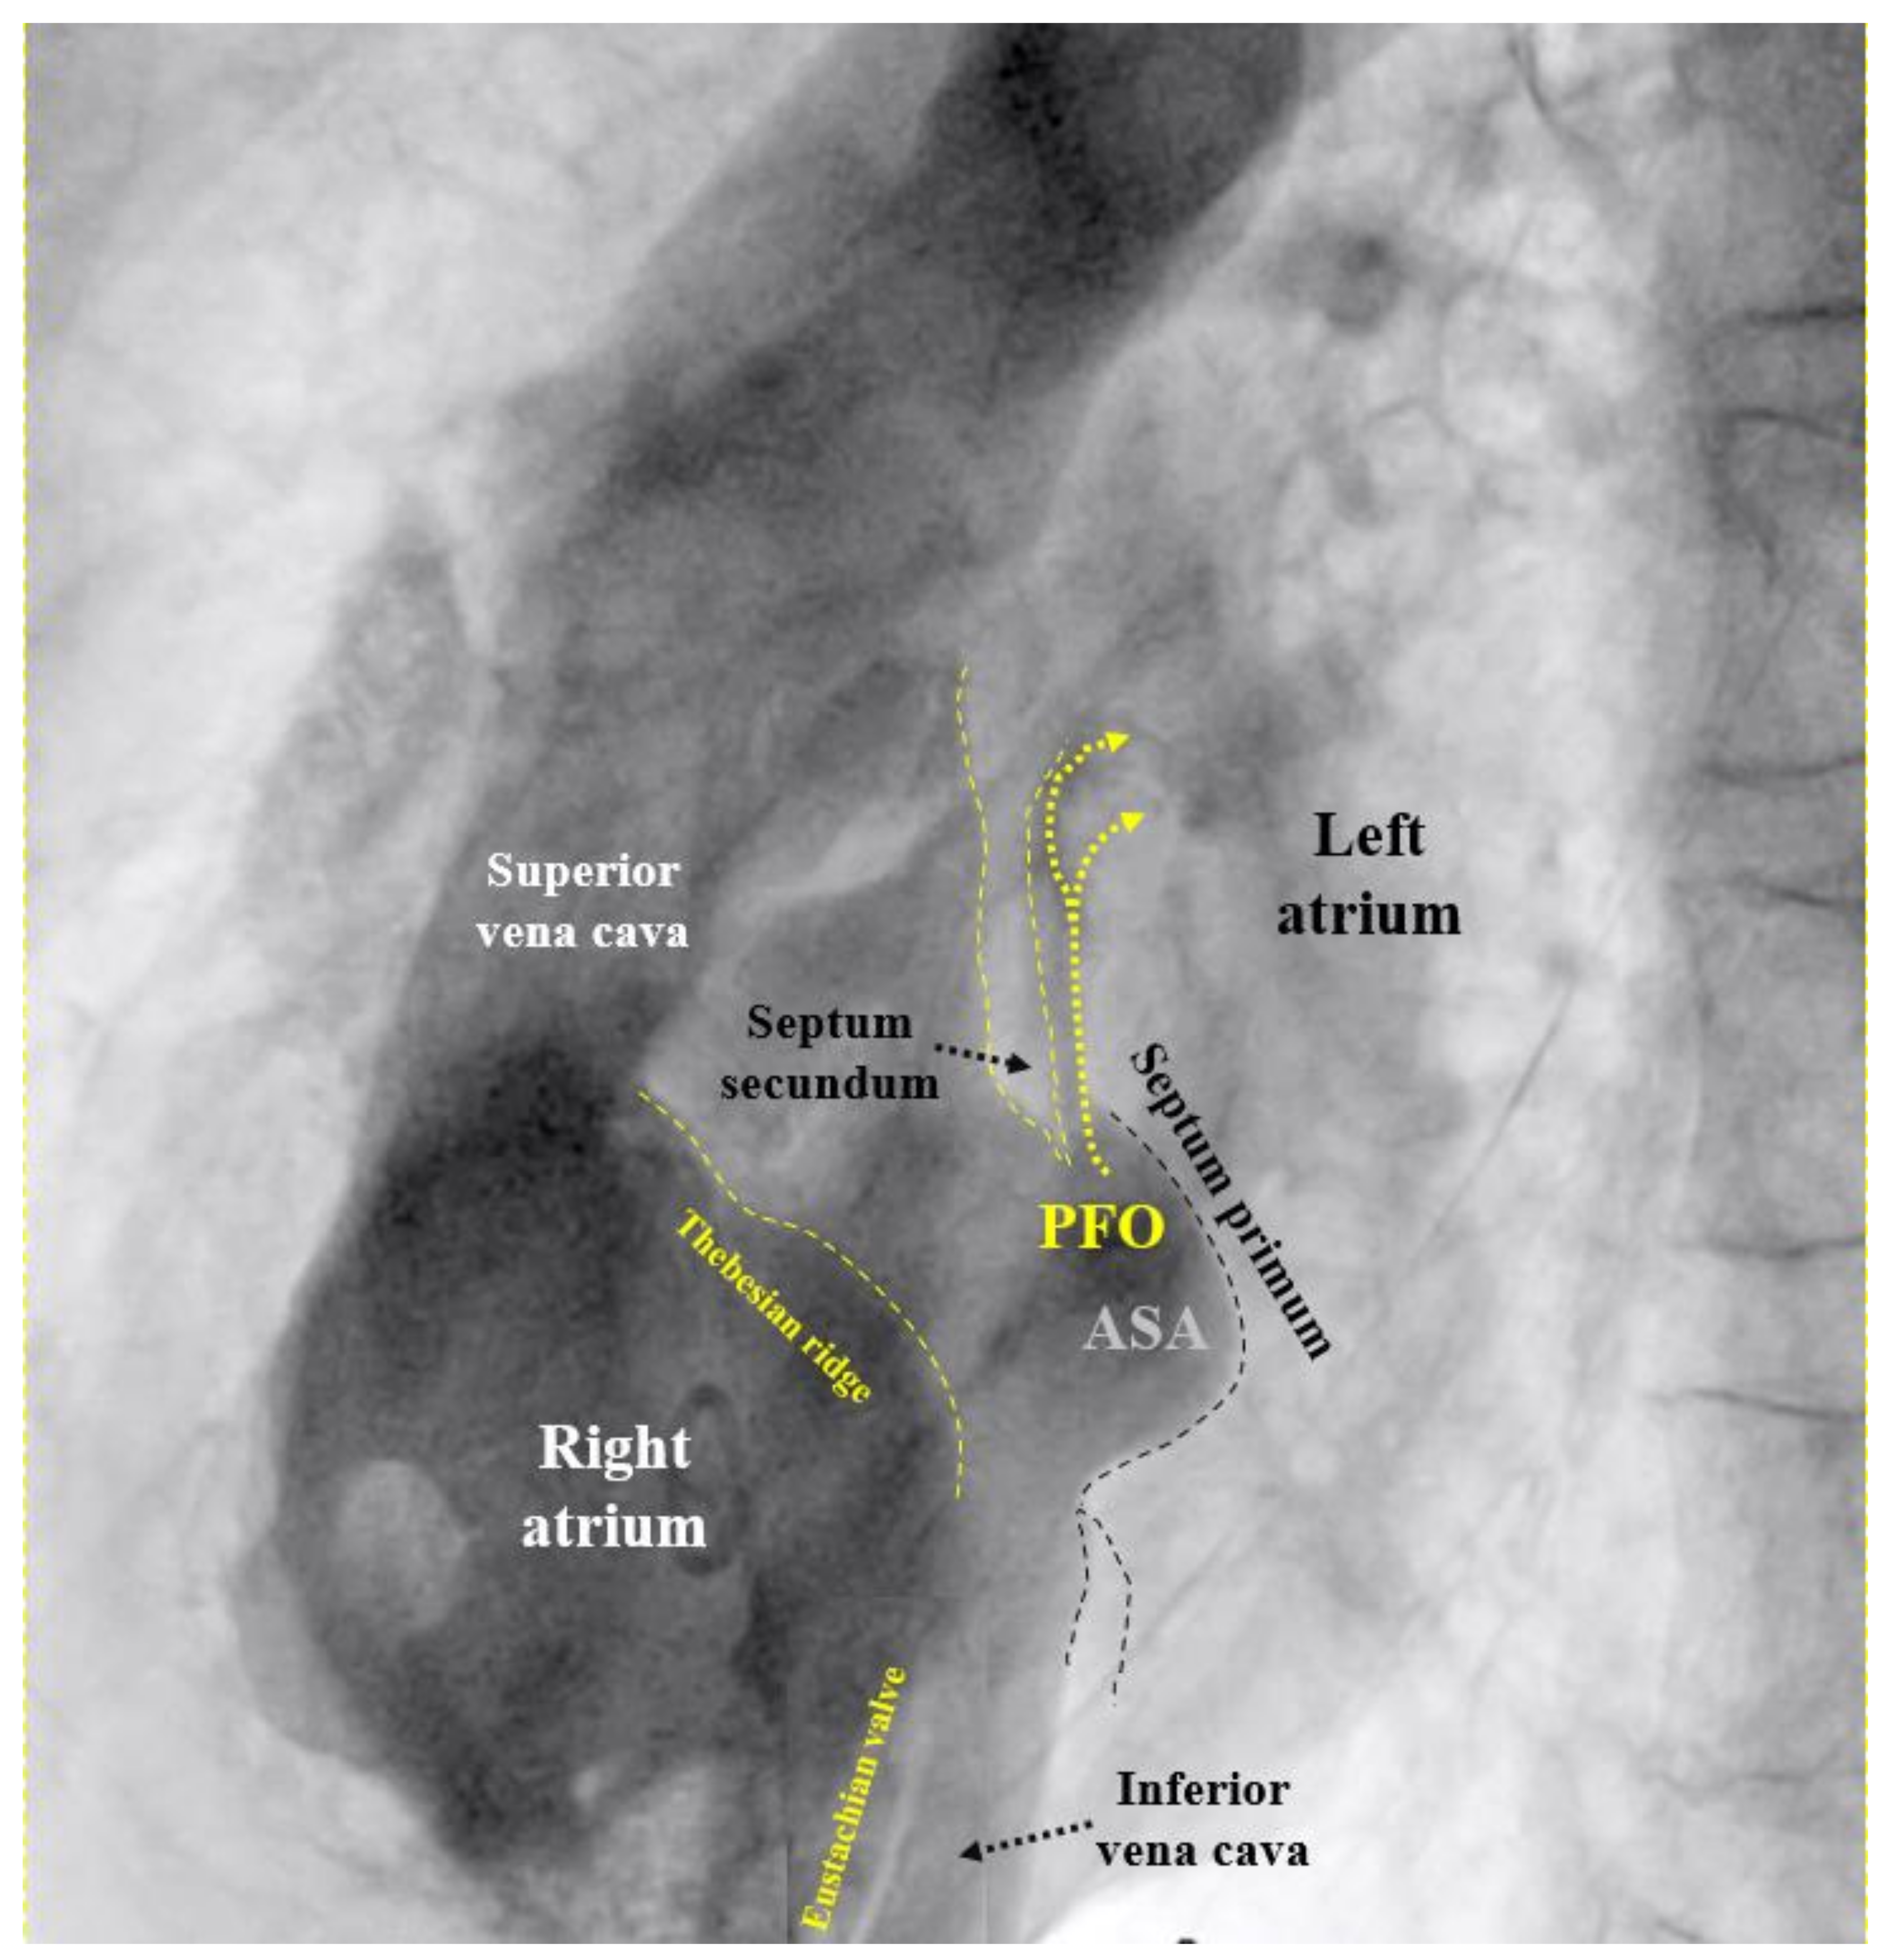

Figure 1. Fluoroscopic contrast imaging of patent foramen ovale (PFO) (left anterior oblique view). All important features are visible, including the Eustachian valve and the Thebesian ridge, a ledge in the free wall of the right atrium, confoundable with the atrial septum. ASA = atrial septal aneurysm.

If the PFO cannot be passed despite changing direction and position of the multipurpose catheter, the U-tip wire may be removed and the tip straightened by scratching the back of the curve with the thumb nail. Should the now straight wire still not pass, the PFO is searched for with the tip of the multipurpose catheter. If even that fails, a right atriogram with contrast medium is performed to understand the anatomy (Figure 1). The initial attempt to pass the atrial septum with a U-tip wire tries to take advantage of the fact that the U-tip wire can only pass through the slit-like PFO. A straight wire or a catheter may inadvertently pass through a tiny atrial septal defect (ASD) in the septum primum. Small cribriform ASDs often go unnoticed in prior echocardiograms.

MI. MI by paradoxical embolism through a PFO must be one of the most frequently misdiagnosed problems in cardiology.50 This is particularly vexing because it is easily preventable by PFO closure. The cardiologists are the ones to blame for this oversight. In the wake of the bad example of neurologists who for nebulous reasons want to have excluded all other potential causes for stroke before scouting for a PFO, cardiologists think of all imaginable causes for a MI before considering paradoxical embolism. In the absence of obvious atherosclerosis (the prime suspect), spontaneous coronary dissection, protracted spasm, or drug abuse are pondered, searched for, or incriminated right off the bat, but not a PFO. The mentioned fact goes ignored that atherosclerosis, age, and systemic disorders promote rather than exclude paradoxical embolism of a venous clot. Only a minority of interventional cardiologists list a PFO among the acknowledged causes for MI. The amount of blood supply per minute to the coronary arteries is about 220 ml/minute at rest. This corresponds to almost a third of that to the brain (roughly 750 ml/minute). Both organs are equally jeopardized by the small clots typically passing through a PFO. Limbs and visceral organs require larger clots for serious ischemic harm. In brain and heart, there are silent embolisms thanks to unimportant areas, pre-existing tissue scars, or collateralized territories. Accounting for all that, one should attribute to a PFO roughly one MI per three cerebral events. This has yet to take into account that neurology significantly underdiagnoses PFO mediated cerebral events. Typically, they are ruled out by default in patients with the highest respective risk. The number of correctly diagnosed PFO mediated MIs should probably be at least hundredfold higher than it currently is. Any acute MI looking even remotely embolic, should prompt a search for a PFO, once the coronary situation is managed. This can be accomplished with a right heart catheterization at the end of the primary coronary percutaneous intervention. Rather than directly probing the PFO with a wire or a catheter as described above, a right atrial injection is preferable (Figure 1). There is a small but concerning risk of a thrombus saddling the PFO,24 part of which just broke off and caused the acute MI. Excluding or proving and closing a PFO in that way adds a few minutes to the coronary case and is doable day or night. It does not really increase the overall risk of the procedure but can do a lot of good. It makes sense in embolic looking MIs irrespective of whether or not they were indeed caused by the PFO. The next MI could well be and a mechanical vaccination against paradoxical embolism is never unwarranted. By the way, screening for a PFO with a right heart catheter is less uncomfortable for the patient than with a TEE. The characteristics of the PFO needed to select the appropriate device size (Figure 4) can be equally well depicted with such a contrast medium study (Figure 1). A combined coronary intervention and PFO closure is in the vetted interest of patients.

To screen for dangerous PFOs, i.e., large ones or those associated with an ASA,8 a Eustachian valve,9–12 or a Chiari network,13 a bubble test during a TTE suffices (Figure 5). The contrast liquid has to be injected at the end of a sustained Valsalva maneuver. A Valsalva maneuver or pressing into the belly by a medical person during TEE if a sedated patient cannot perform a Valsalva maneuver, blocks the backflow of the venous blood into the thorax. Both atria get volume depleted within 10 to 20 s. Upon Valsalva release, the venous blood gushes into the right atrium first, thereby pushing the PFO open towards the still underfilled left atrium.

The venous inflow into the right atrium from the inferior vena cava is directed onto the PFO, even more so in the presence of a Eustachian valve9–12 or a Chiari network.13 The inflow of the superior vena cava is not. Hence, injecting the contrast medium in a leg vein would be ideal.14,15 Yet, this is impractical and under most circumstances an arm vein has to do. A state-of-the-art bubble test during a TEE or a transcranial Doppler examination16 in adddition detects small PFOs that harbor a smaller (albeit still relevant) risk for paradoxical embolism.